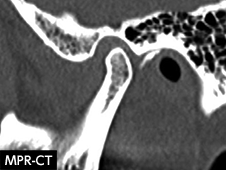

図❷ 初診時のCT画像(左側顎関節部矢状断)

画像所見: MRIのT2WIで、左側顎関節上関節腔において高信号領域のなかに複数の低信号領域が散見された。CT像では下顎頭の変形や滑膜肥厚は認めず、石灰化を伴う病変もみられなかった(図❶❷)。